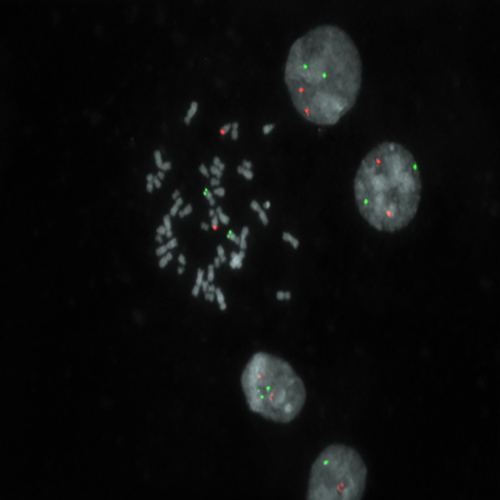

Hybridization of MYC/IGH fusion probe to a metaphase spread showing normal pattern (2R2G).

The translocation t(8;14)(q24;q32) is the characteristic chromosomal aberration of Burkitt's-type of lymphomas. This translocation fuses the MYC gene at 8q24 next to the IGH locus at 14q32, resulting in overexpression of the transcription factor MYC. Detection of the t(8;14) is aimed to help in the diagnostic process of patients with high-grade B-cell lymphomas because treatment strategies differ between Burkitt and other high-grade lymphomas. The MYC/IGH t(8;14)(q24;q32) specific FISH probe is optimized to detect the reciprocal translocation t(8;14) in a dual-color, dual-fusion assay.